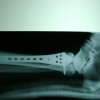

Cuando se necesita cirugía, es probable que esta implique el uso de clavijas de metal, tornillos o placas para sostener los huesos en su lugar mientras la fractura se consolida. Los elementos de soporte pueden ser temporales o permanentes.